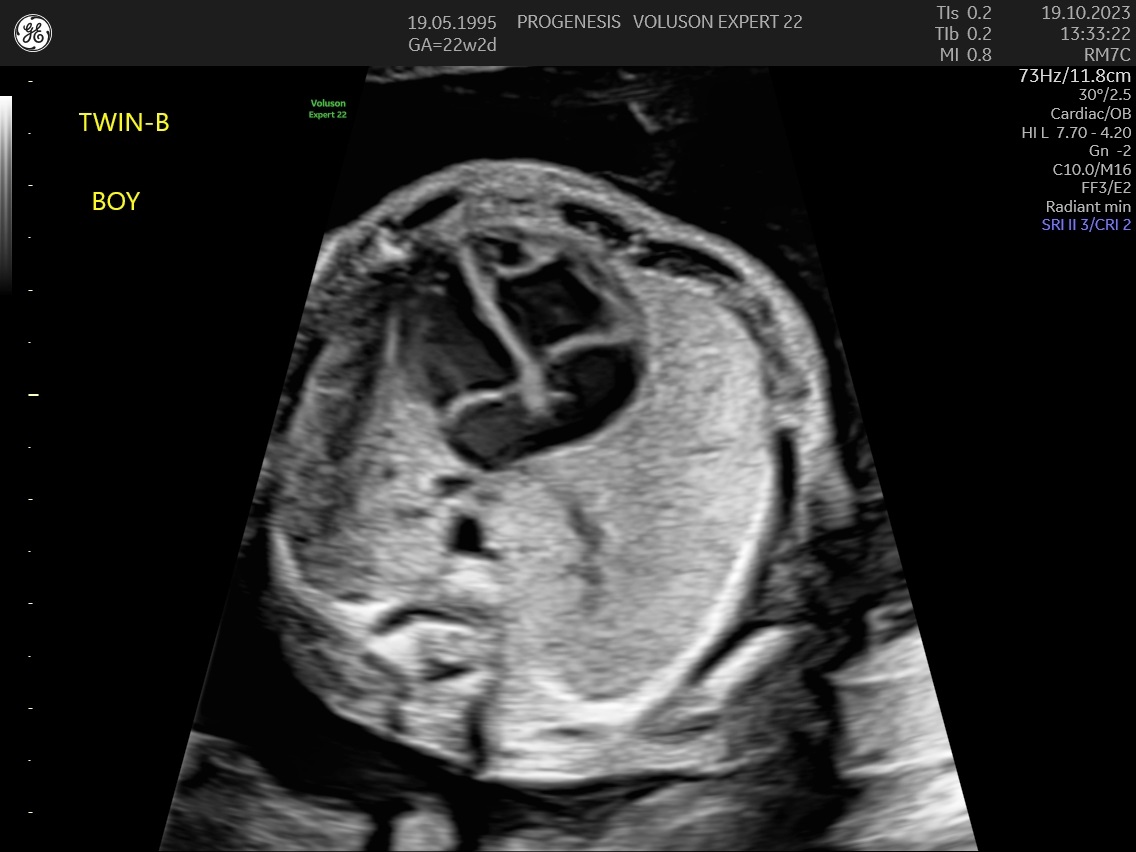

α) Η λεπτομερής αξιολόγηση της εμβρυϊκής ανατομίας, όπου αναγνωρίζονται τυχόν ανατομικές ανωμαλίες.

γ) Ο έλεγχος της ανάπτυξης του εμβρύου, του πλακούντα, του ομφαλίου λώρου και του αμνιακού υγρού.